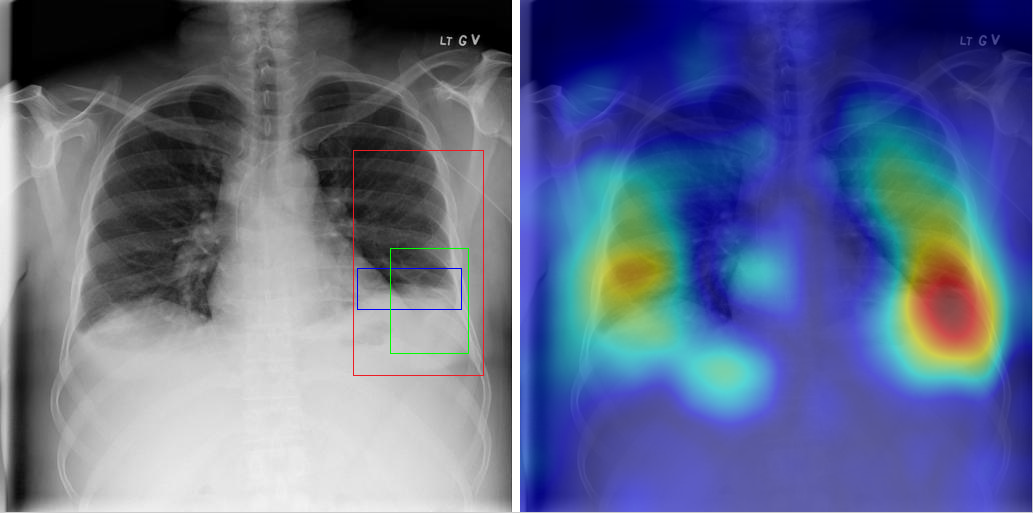

Table 8 to Table 15 illustrate localization results from each of 8 disease classes together with associated report and mined disease keywords. The heatmaps overlay on the original images are shown on the right. Correct bounding boxes (in green), false positives (in red) and the groundtruth (in blue) are plotted over the original image on the left.

In order to quantitatively demonstrate how informative those heatmaps are, a simple two-level thresholding based bounding box generator is adopted here to catch the peaks in the heatmap and later generated bounding boxes can be evaluated against the ground truth. Each heatmap will approximately results in 1-3 bounding boxes. We believe the localization accuracy and AFP (shown in Table 7) could be further optimized by adopting a more sophisticated bounding box generation method, e.g. selective search [47] or Edgebox [18]. Nevertheless, we reserve the effort to do so, since our main goal is not to compute the exact spatial location of disease patterns but just to obtain some instructive location information for future applications, e.g. automated radiological report generation. Take the case shown in Table 8 for an example. The peak at the lower part of the left lung region indicates the presence of “atelectasis”, which confer the statement of “…stable abnormal study including left basilar infilrate/atelectasis, …” presented in the impression section of the associated radiological report. By combining with other information, e.g. a lung region mask, the heatmap itself is already more informative than just the presence indication of certain disease in an image as introduced in the previous works, e.g. [42].

Radiology report Keyword Localization Result

findings: no appreciable change since XX/XX/XX. small right pleural effusion. elevation right hemidiaphragm. diffuse small nodules throughout the lungs, most numerous in the left mid and lower lung. impression: no change with bilateral small lung metastases. Effusion; Nodule [Uncaptioned image]

Table 10: A sample of chest x-ray radiology report, mined disease keywords and localization result from the “Effusion” Class. Correct bounding box (in green), false positives (in red) and the ground truth (in blue) are plotted over the original image.